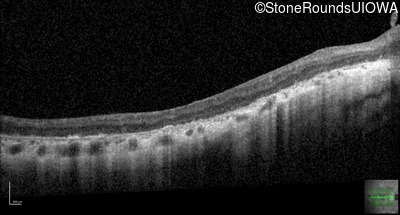

Visit at age: 36 years

Optical Coherence Tomography - Left - 20/70 +1

Exemplar / OCT Stack

OCT Stack